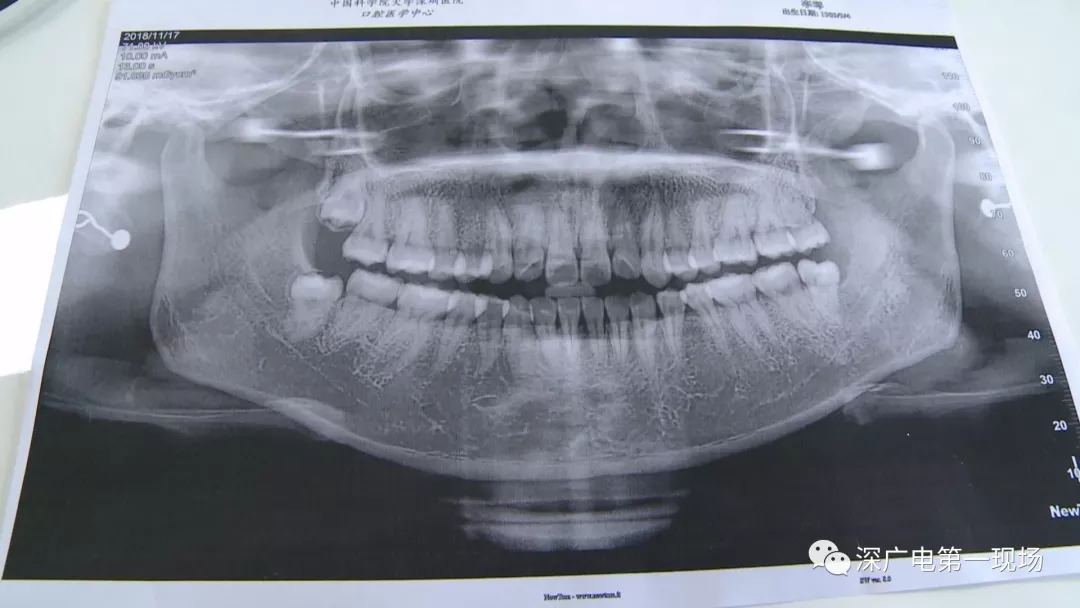

針對李女士的情況,醫(yī)生介紹,當時要想拔出李女士的這顆智齒,難度還是很大的,屬于復(fù)雜智齒的拔除術(shù)。她的風險在于距離神經(jīng)管近,同時這顆牙齒完全埋在牙床最后的位置,直接往外拔,會加大頜骨的風險,因此需要先切開,讓牙齒暴露后,切小再慢慢地拔出。